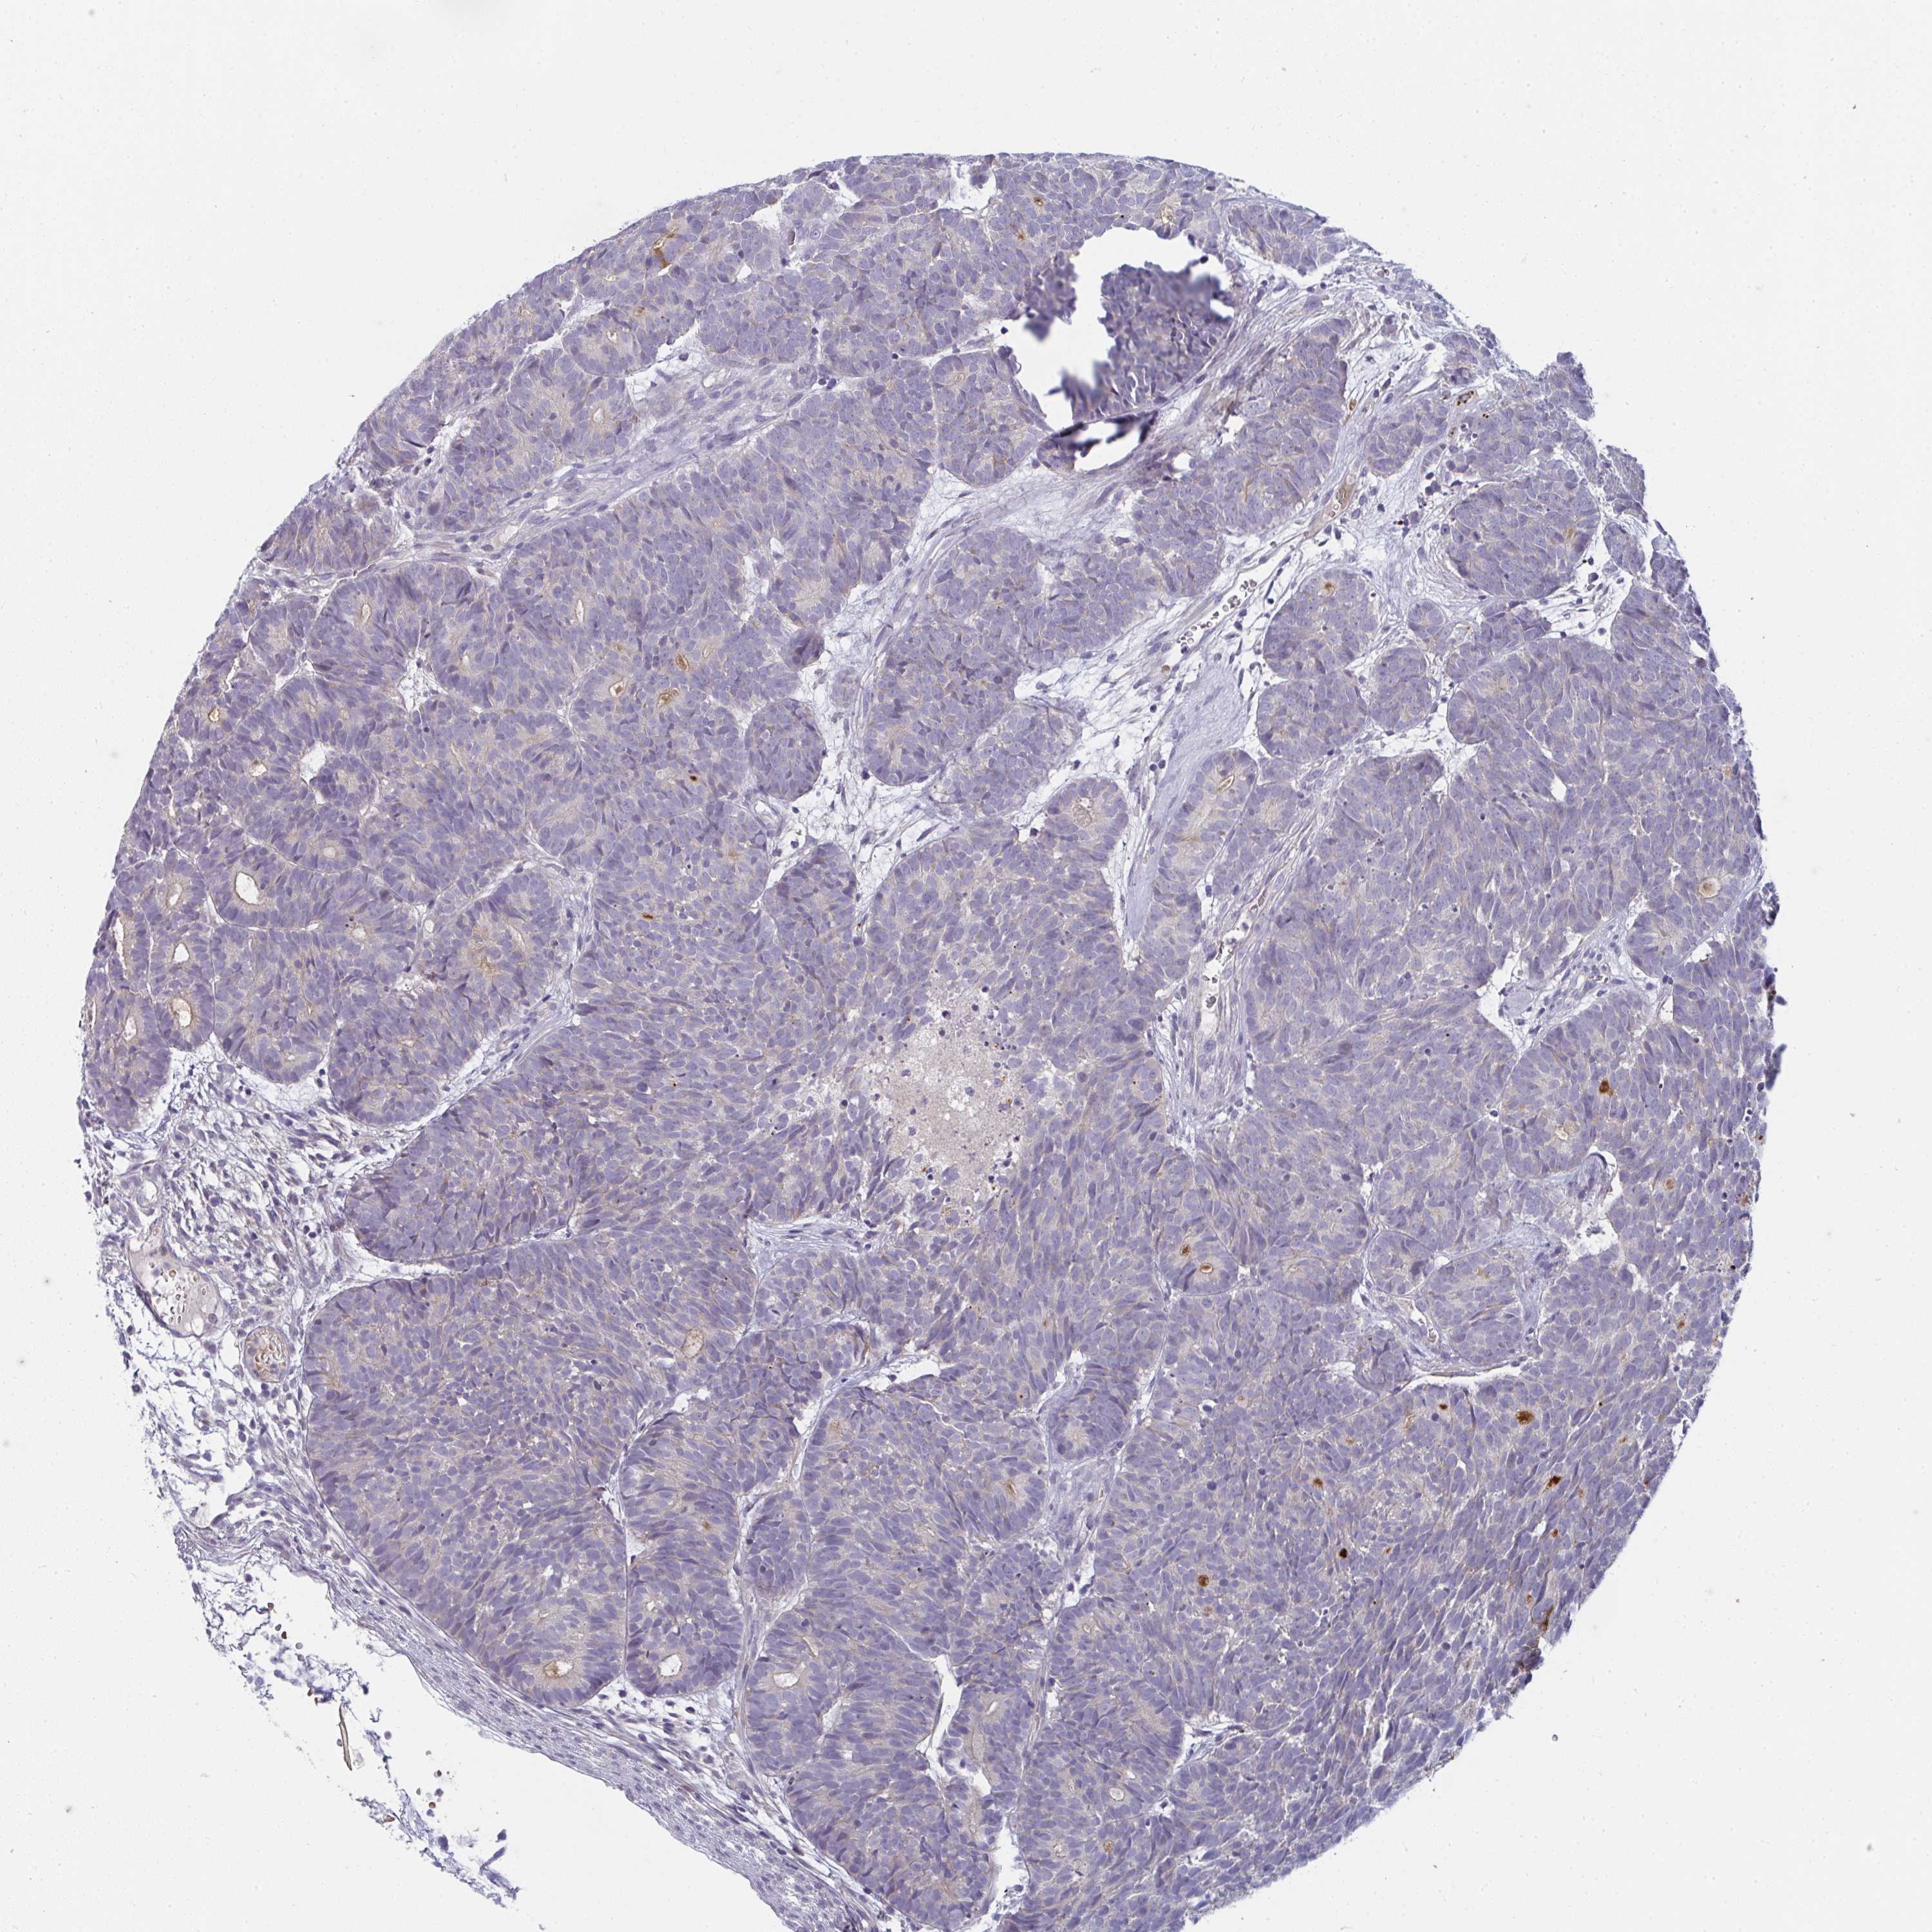

HEAD AND NECK CANCER - Protein expressioni

A mouse-over function shows sample information and annotation data. Click on an image to view it in a full screen mode. Samples can be filtered based on level of antibody staining by selecting one or several of the following categories: high, medium, low and not detected. The assay and annotation is described here.

Antibody stainingi

Antibody staining in the annotated cell types in the current human tissue is reported as not detected, low, medium, or high, based on conventional immunohistochemistry profiling in selected tissues. This score is based on the combination of the staining intensity and fraction of stained cells.

Each image is clickable and will lead to virtual microscopy that enables deeper exploration of all samples and also displays staining intensity scores, fraction scores and subcellular localization as well as patient and tissue information for each sample.

Antibody HPA049911

Antibody CAB010161

Staining

High

Medium

Low

Not detected

Intensity

Strong

Moderate

Weak

Negative

Quantity

>75%

75%-25%

<25%

None

Location

Nuclear

Cytoplasmic/membranous

Cytoplasmic/membranous,nuclear

Squamous cell carcinoma, NOS